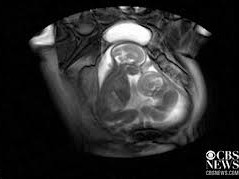

Các nhà nghiên cứu đã quay được một đoạn video thú vị về hai em bé tranh giành nhau chỗ trong bụng mẹ để duỗi chân thoải mái.